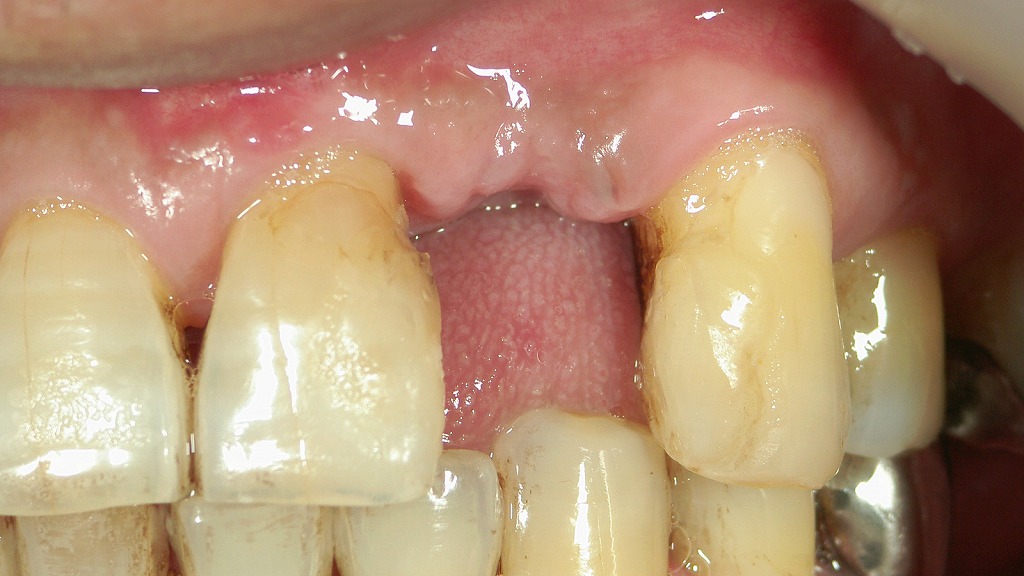

🦷 保険のブリッジ症例の例:前歯6本連結のブリッジ

- 治療範囲:右上2番から左上4番までの6本を連結

- 欠損歯:右上1番と左上3番が欠損(青丸で表示)

- 構造:欠損部にポンティック(人工歯)、両隣の歯を支台歯としてブリッジを固定

前歯保険適用ブリッジ正面観

6連のブリッジで5本が硬質レジン前装冠で作られ、1本は金属で作られています。

硬質レジンは経年劣化が著しく変色や着色、破折が認められます。

前歯保険適用ブリッジ咬合面観

咬合面からみりとブリッジの内側はすべて金属になっているのが分かります。左上4番だけは金属冠で作られています。